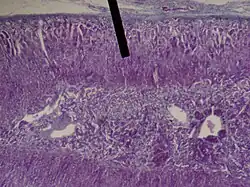

The zona fasciculata (sometimes, fascicular or fasciculate zone) constitutes the middle and also the widest zone of the adrenal cortex, sitting directly beneath the zona glomerulosa. Constituent cells are organized into bundles or "fascicles".